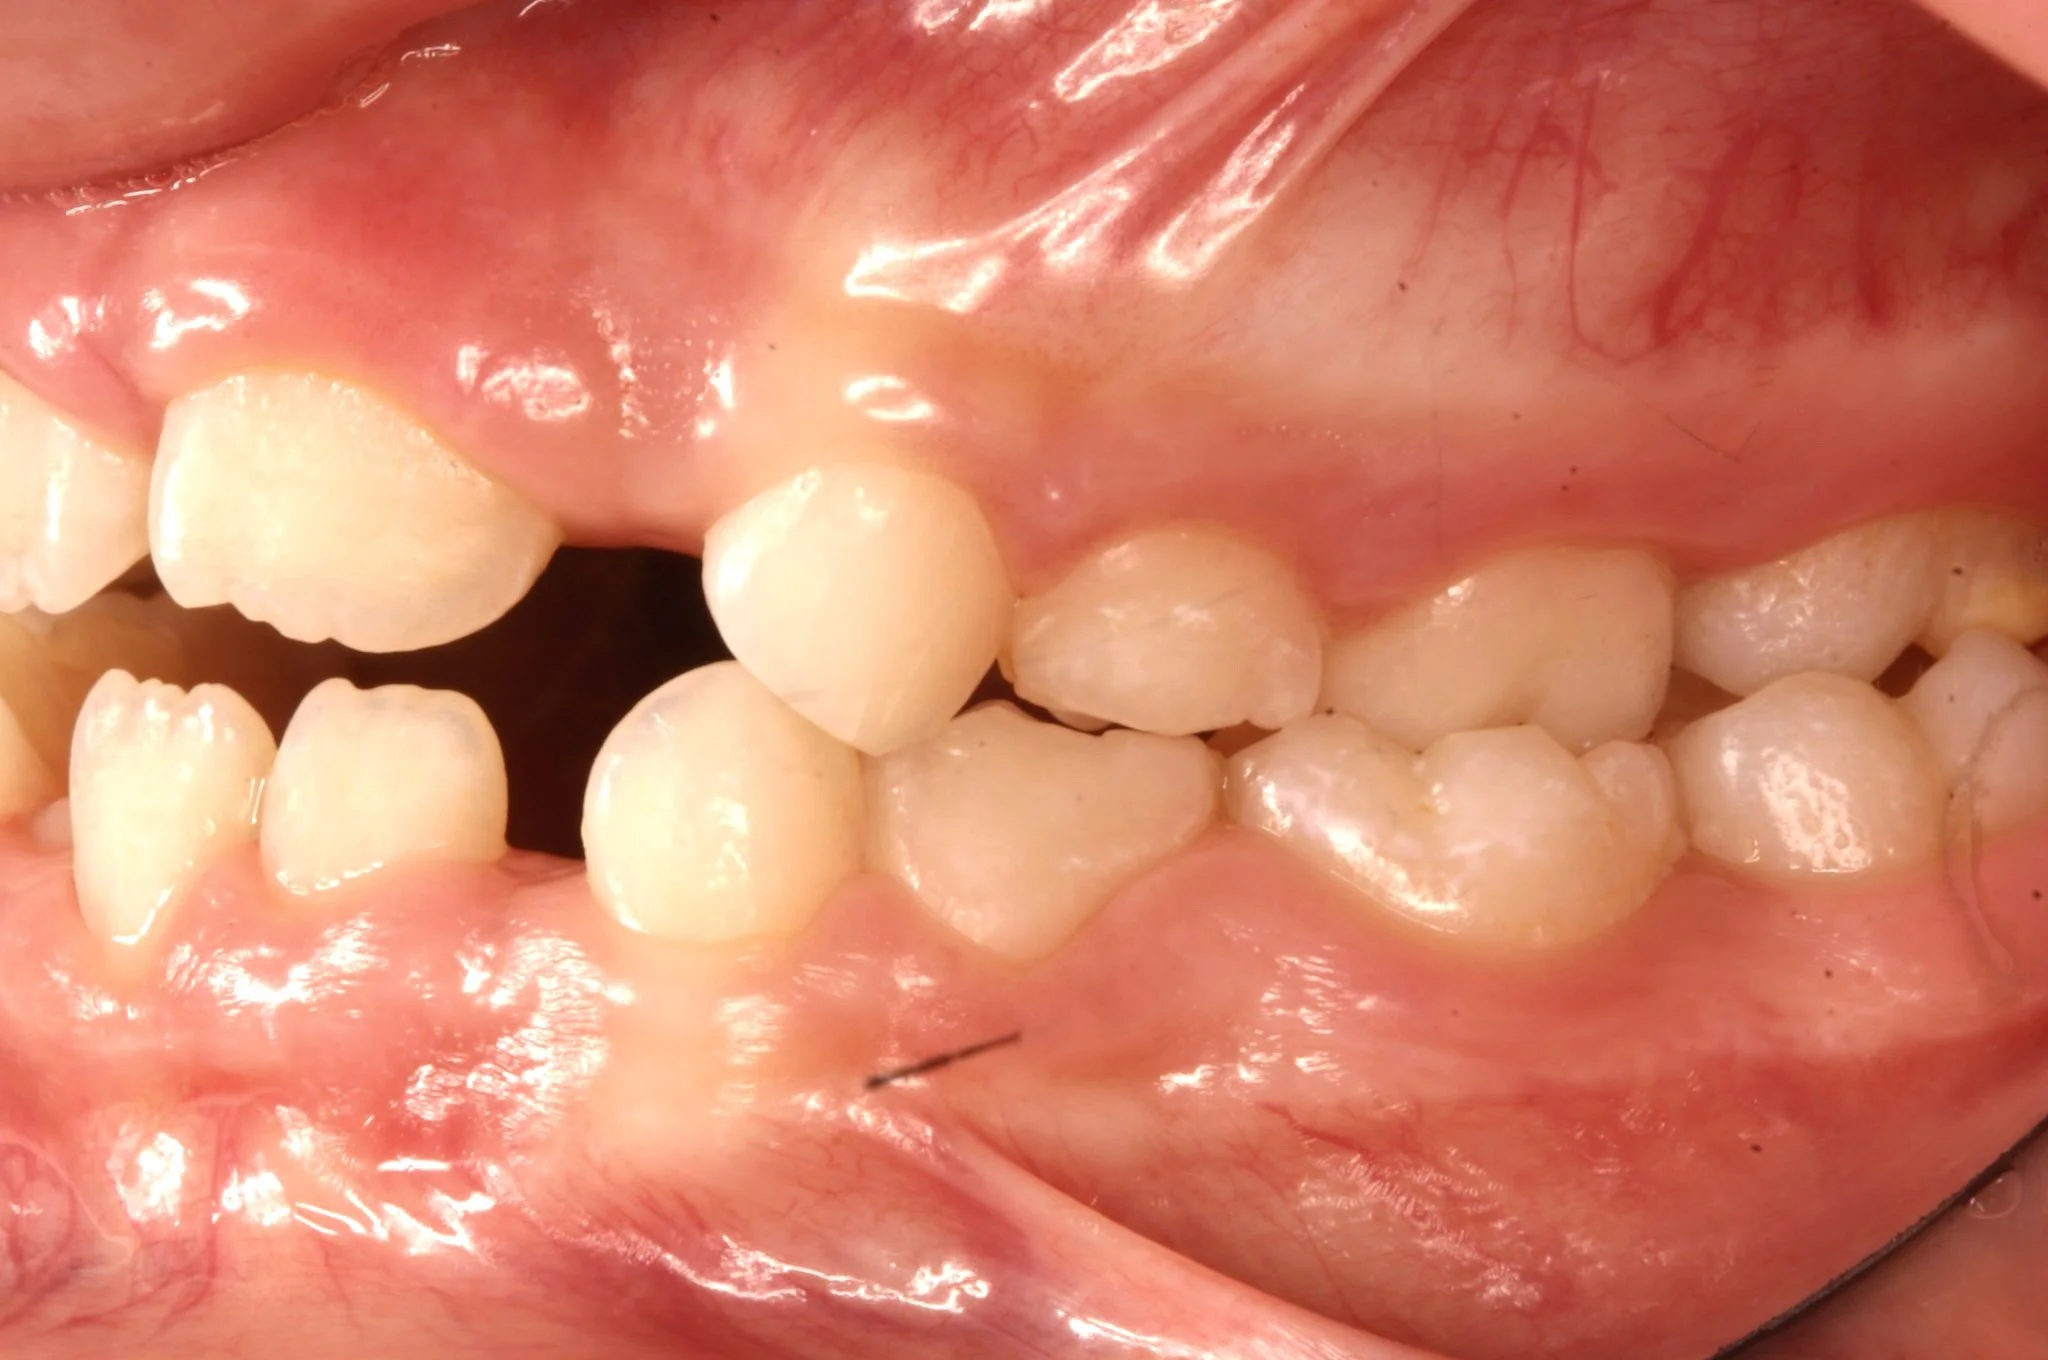

BEFORE

Caso di una paziente con morso aperto iniziale e palato stretto, trattato in giovane età con terapia intercettiva mediante espansione rapida del palato. Successivamente, in adolescenza, è stata sottoposta a trattamento ortodontico fisso in dentatura permanente.